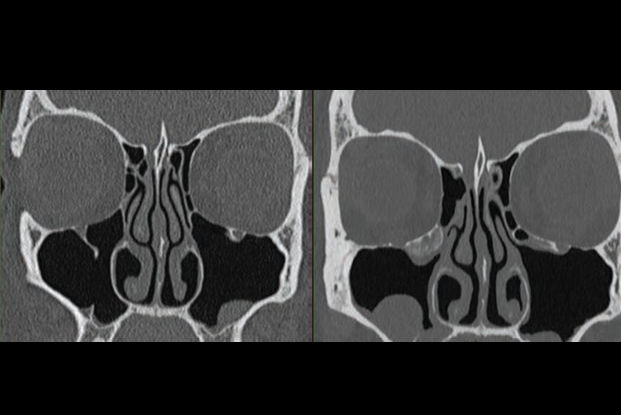

The biggest story of the year has been COVID-19 (in fact, that's why we're all at home this week instead of in Chicago). And perhaps the go-to imaging modality for the diagnosis of COVID-19 patients has been CT. In a scientific session on Sunday afternoon, researchers from multiple groups discussed how they have been using CT to manage patients, with at least two groups reporting on their use of AI.